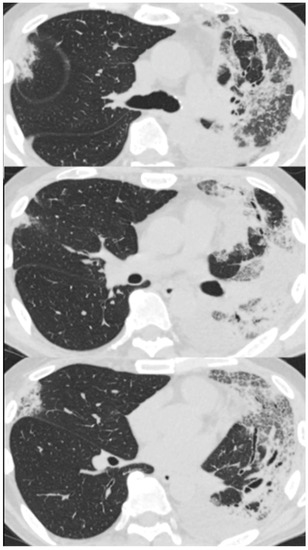

On arrival at our hospital, his blood pressure, pulse rate, and oxygen saturation were normal; however, his body temperature was 37.7 °C. The patient’s respiratory rate was 18 breaths/min. Chest auscultation revealed coarse crackles throughout the left lung field. A chest X-ray showed consolidation in the left lung field. (Figure 3) A chest CT scan showed consolidation in the entire left lung field and leftward deviation of the mediastinum, due to contractile changes. A small area of consolidation was seen just below the peripheral pleura in the right upper and middle lobes. (Figure 4) His blood tests showed leukocytosis (18,300/μL), eosinophilia (26.5%), and high C-reactive protein levels (18.12 mg/dL). KL-6 and SP-D levels were normal. Tests for beta-D-glucan, aspergillus antigen, interferon-gamma release assays, antineutrophil cytoplasmic antibody, antinuclear antibody, anti-aminoacyl-tRNA synthetase antibody, Anti-Scl-70 antibody, and anti-cyclic citrullinated peptide antibody were all negative. The PCR test for coronavirus disease 2019 was negative.

Figure 4. Chest computed tomography of a 59-year-old man with dyspnea scan showed consolidation in the entire left lung field and a leftward deviation of the mediastinum due to contractile changes. A slight consolidation was seen just below the peripheral pleura in the right upper and middle lobes.